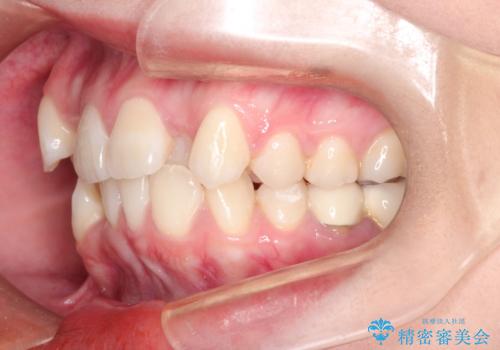

八重歯のワイヤーによる抜歯矯正 矯正治療と並行してセラミック治療も

- 八重歯と前歯のガタガタを主訴に来院されました。

今回の場合も、ブリッジを除去して矯正後にセラミックブリッジを装着しました。